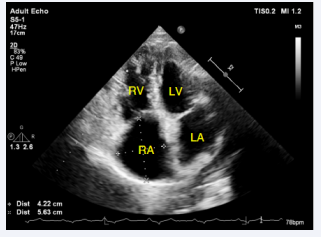

Patient was taken to the catheterization laboratory for ASD secundum type closure using Amplatzer device under TEE guidance. However, during procedure the multipurpose catheter crossed very inferiorly at the level of the coronary sinus (CS) into the LA. The left upper pulmonary vein identified very easily as well as a small CS vein, which is draining from the great cardiac vein. TEE showed that the multipurpose catheter in the LA, however, it did not go through the previously mentioned secundum ASD, raising the possibility of different co-existing septal defect. Procedure was aborted and patient was scheduled for CCTA to better define the septal defect and rule out the presence of PLSVC. CCTA showed a large ASD inferiorly, representing an UCS. The defect is large, measuring 24 mm in length, and both the superior and inferior vena cava are intact. The pulmonary veins drain in the LA. The right pulmonary veins emerge from a single trunk, while the left pulmonary veins emerge from a very short trunk that splits into two branches early on (Figures 6-9).

Cardiac computed tomography angiography (CCTA) in  sagittal display showing a communication between the RA and LA  representing unroofed CS (Arrow). CS, Coronary Sinus.

Figure 7: Cardiac computed tomography angiography (CCTA) in sagittal display showing a communication between the RA and LA representing unroofed CS (Arrow). CS, Coronary Sinus.

Cardiac computed tomography angiography (CCTA) threedimensional reconstruction showing the unroofed dilated CS.

Figure 9: Cardiac computed tomography angiography (CCTA) threedimensional reconstruction showing the unroofed dilated CS.